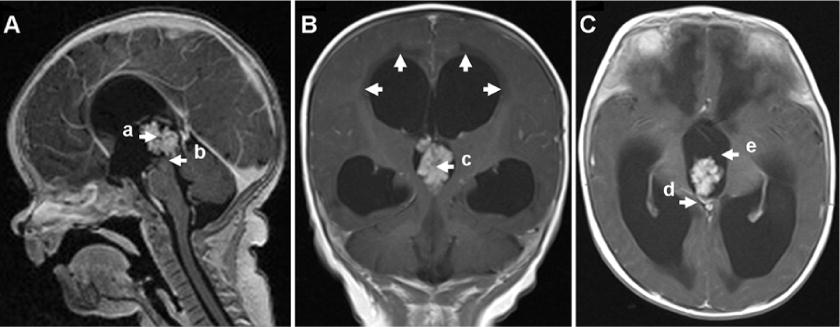

在被我們學(xué)校錄取時,這個男孩仍然不能抬起頭或翻身?;颊咴谛难?、呼吸、消化和泌尿系統(tǒng)方面均無不良反應(yīng)。他的頭圍為46厘米,前囟門是緊繃的。神經(jīng)學(xué)評估顯示會聚性斜視,雙側(cè)上肢和下肢肌力下降至+4,雙側(cè)上肢和下肢肌肉張力下降,上肢和下肢反射亢進(jìn),雙側(cè)巴賓斯基征。眼底鏡檢查為陰性眼底充血。磁共振成像(mri)顯示,三腦室內(nèi)出現(xiàn)了2.12×1.61×1.45厘米大小的不規(guī)則腫塊,增大到2.21厘米。腫塊不規(guī)則,邊界清楚,t1加權(quán)像呈等至低信號,t2加權(quán)像呈輕度高信號。腫塊占據(jù)三腦室后部,壓迫腦室導(dǎo)水管,使四邊形板前部脫位進(jìn)入池內(nèi)。造影劑注射顯示腫塊呈不規(guī)則強(qiáng)化。側(cè)腦室不對稱增大,左腦室大于右腦室。t2加權(quán)和FLAIR像顯示三腦室和側(cè)腦室周圍明顯水腫(圖1)。

圖1:術(shù)前MRI與靜脈造影對比。A:矢狀面顯示腫瘤(A)位于三腦室后部。腫瘤穿透(b)進(jìn)入大腦導(dǎo)水管導(dǎo)致堵塞。B:冠狀圖顯示三腦室菜花樣腫瘤結(jié)節(jié)(c),腦積水。箭頭表示心室周圍水腫。C:軸向圖像顯示腫瘤血管蒂(d)。注意腫瘤與三腦室大小的關(guān)系(e)。